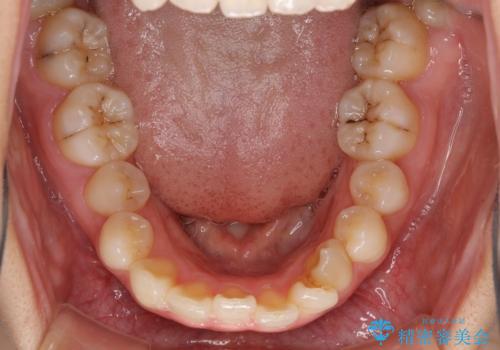

- 前歯のデコボコを気にして来院された患者様です。

叢生と捻転が随所に認められるものの、マウスピースで十分対応可能であったため、インビザラインにて矯正治療を行うこととしました。